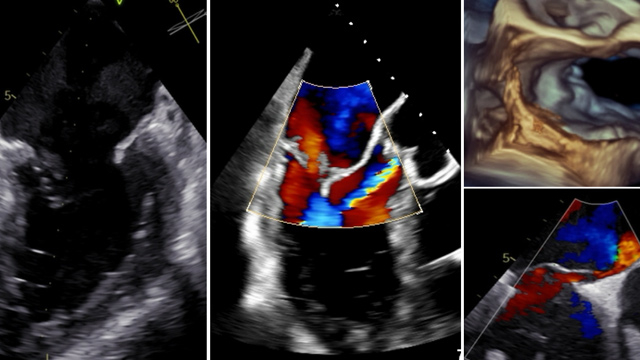

Challenging mitral TEER: Barlow's disease, fibro-elastic deficiency & abnormal valve morphology

17 Nov 2025 – From PCR London Valves 2025

This session examines the feasibility and technical considerations of mitral transcatheter edge-to-edge repair (TEER) in complex anatomical and pathological scenarios. Topics include applications in Barlow's disease, fibro-elastic deficiency, congenital heart anomalies, Anderson-Fabry disease, and post-cardiac transplantation, providing valuable insights into expanding TEER indications and overcoming anatomical...

Mitral interventions in shock

17 Nov 2025 – From PCR London Valves 2025

This session highlights the intricacies of mitral valve interventions in the context of cardiogenic shock. It addresses complex cases including left-to-right shunts post septal puncture, severe ischemic mitral insufficiency with small valve anatomy, emergency mitral TEER for papillary muscle rupture, and bridging strategies to surgery.